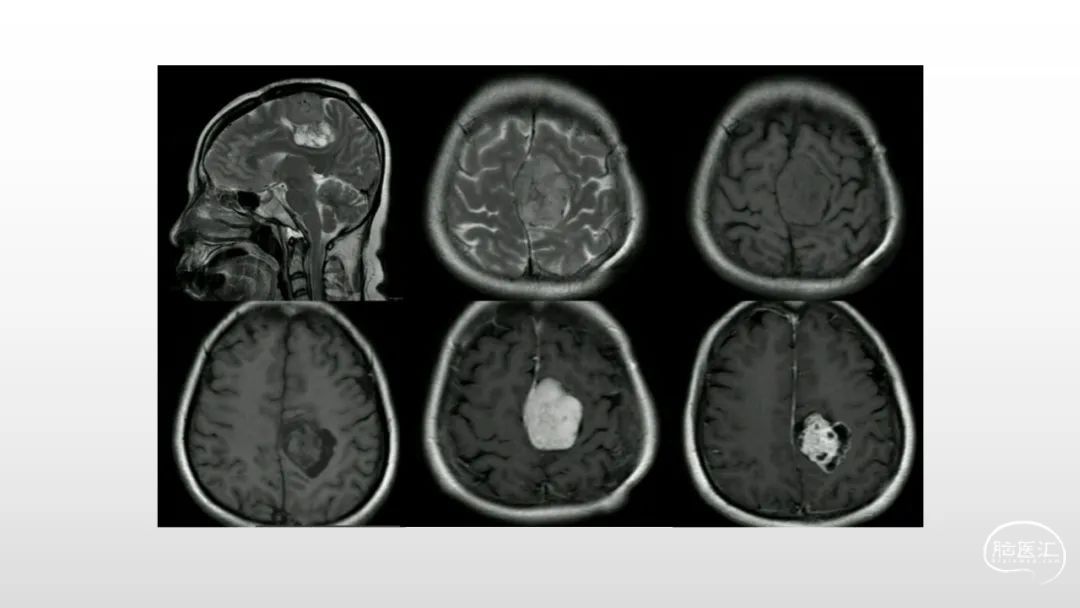

颅脑影像诊断基础知识讲座:脑膜病变

马洪舟

菏泽市立医院